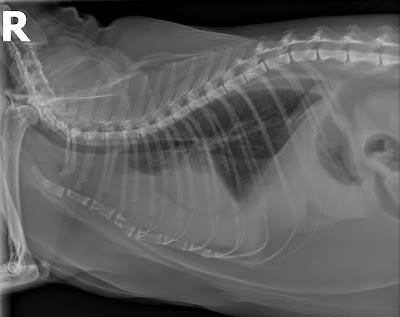

影像顯示胸腔內有很多液體:

緊急抽掉大部分的胸水後,貓咪感覺好一點,抽出的胸水經細菌培養與分析,確認為『乳糜液』。主要由於胸腔內的胸管阻塞或破裂導致乳糜液流進胸腔。